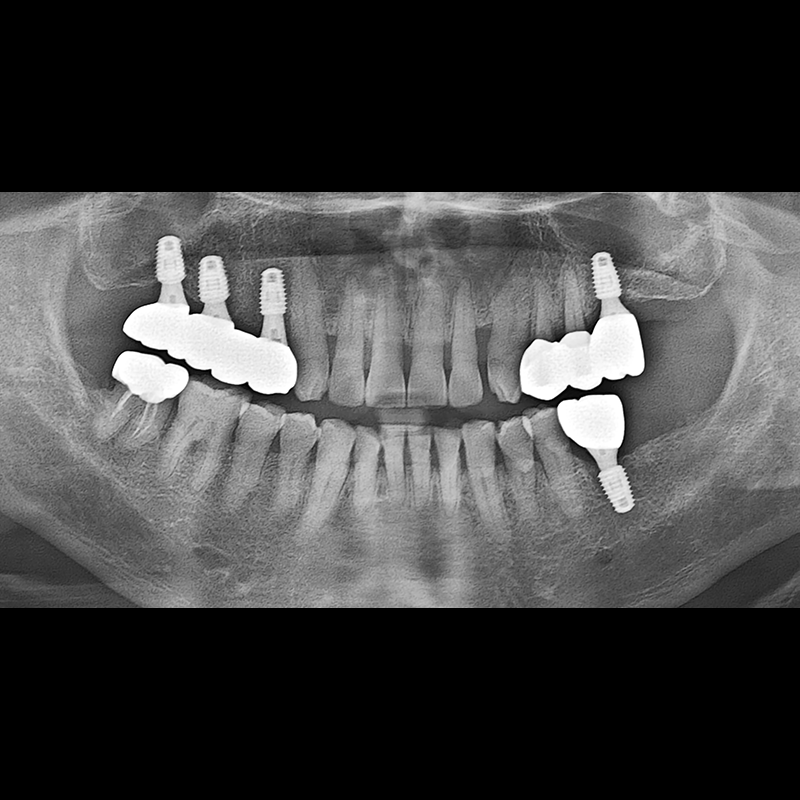

BEFORE AFTER

임플란트 전후사진 2025.05.30

결손된 치아 부분과 살리기 힘든 치아 위치에 임플란트를 식립하였습니다.